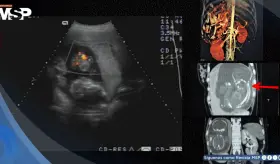

Se confirmó un embarazo intrahepático de 23 semanas, una condición extremadamente rara en la que el feto se desarrolló dentro del lóbulo hepático derecho, con irrigación directa de la arteria hepática y una placenta firmemente adherida al tejido del hígado.